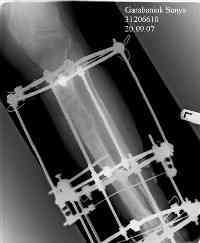

Владимир, свободная костная пластика на фоне свища вряд ли оправдана. Почему не рассматриваете вариант транспорта кости по Илизарову? Что собираетесь делать с латентной инфекцией? Одни антибиотики не помогут, необходима полноценная хирургическая обработка, Мы бы подумали о цементном спейсере с антибиотиками, бусах. После купирования инфекции переходить к замещению

дефекта: за счет удлинения концов б\б кости или тибиализации м\б. На начальном этапе фиксация только в аппарате, в последствие для удержания достигнутого можно перейти на фиксацию интрамедуллярным штифтом (см. вложенные файлы)

После решения той проблемы, для которой нужен аппарат, его можно сменить на внутренний фиксатор.